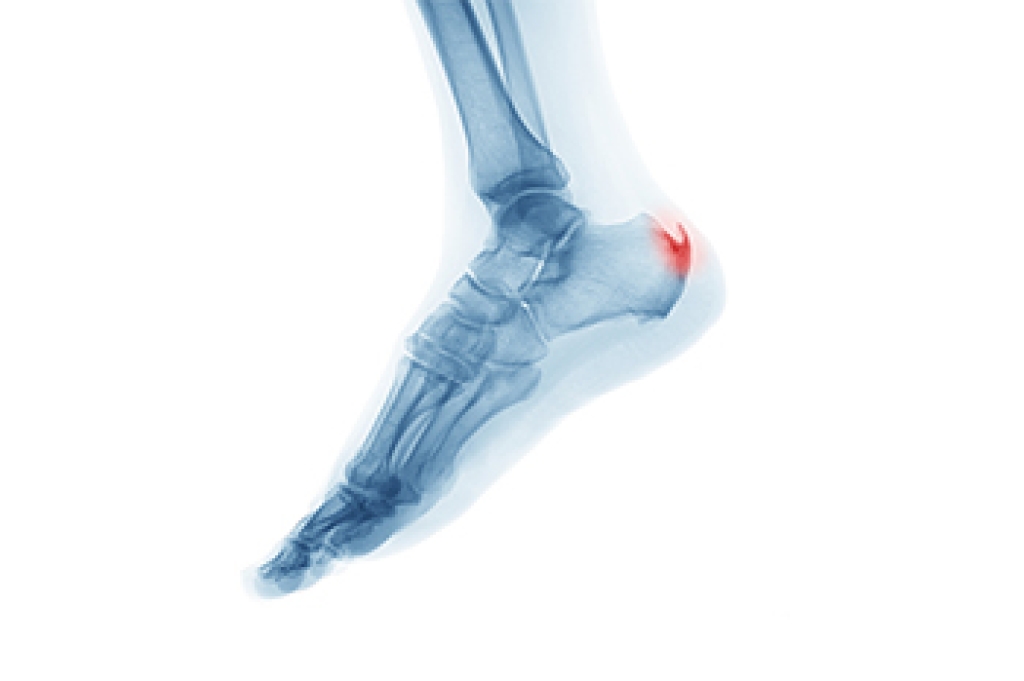

Understanding the Plantar Calcaneal Spur

Heel spurs are formed by calcium deposits on the back of the foot where the heel is. This can also be caused by small fragments of bone breaking off one section of the foot, attaching onto the back of the foot. Heel spurs can also be bone growth on the back of the foot and may grow in the direction of the arch of the foot.